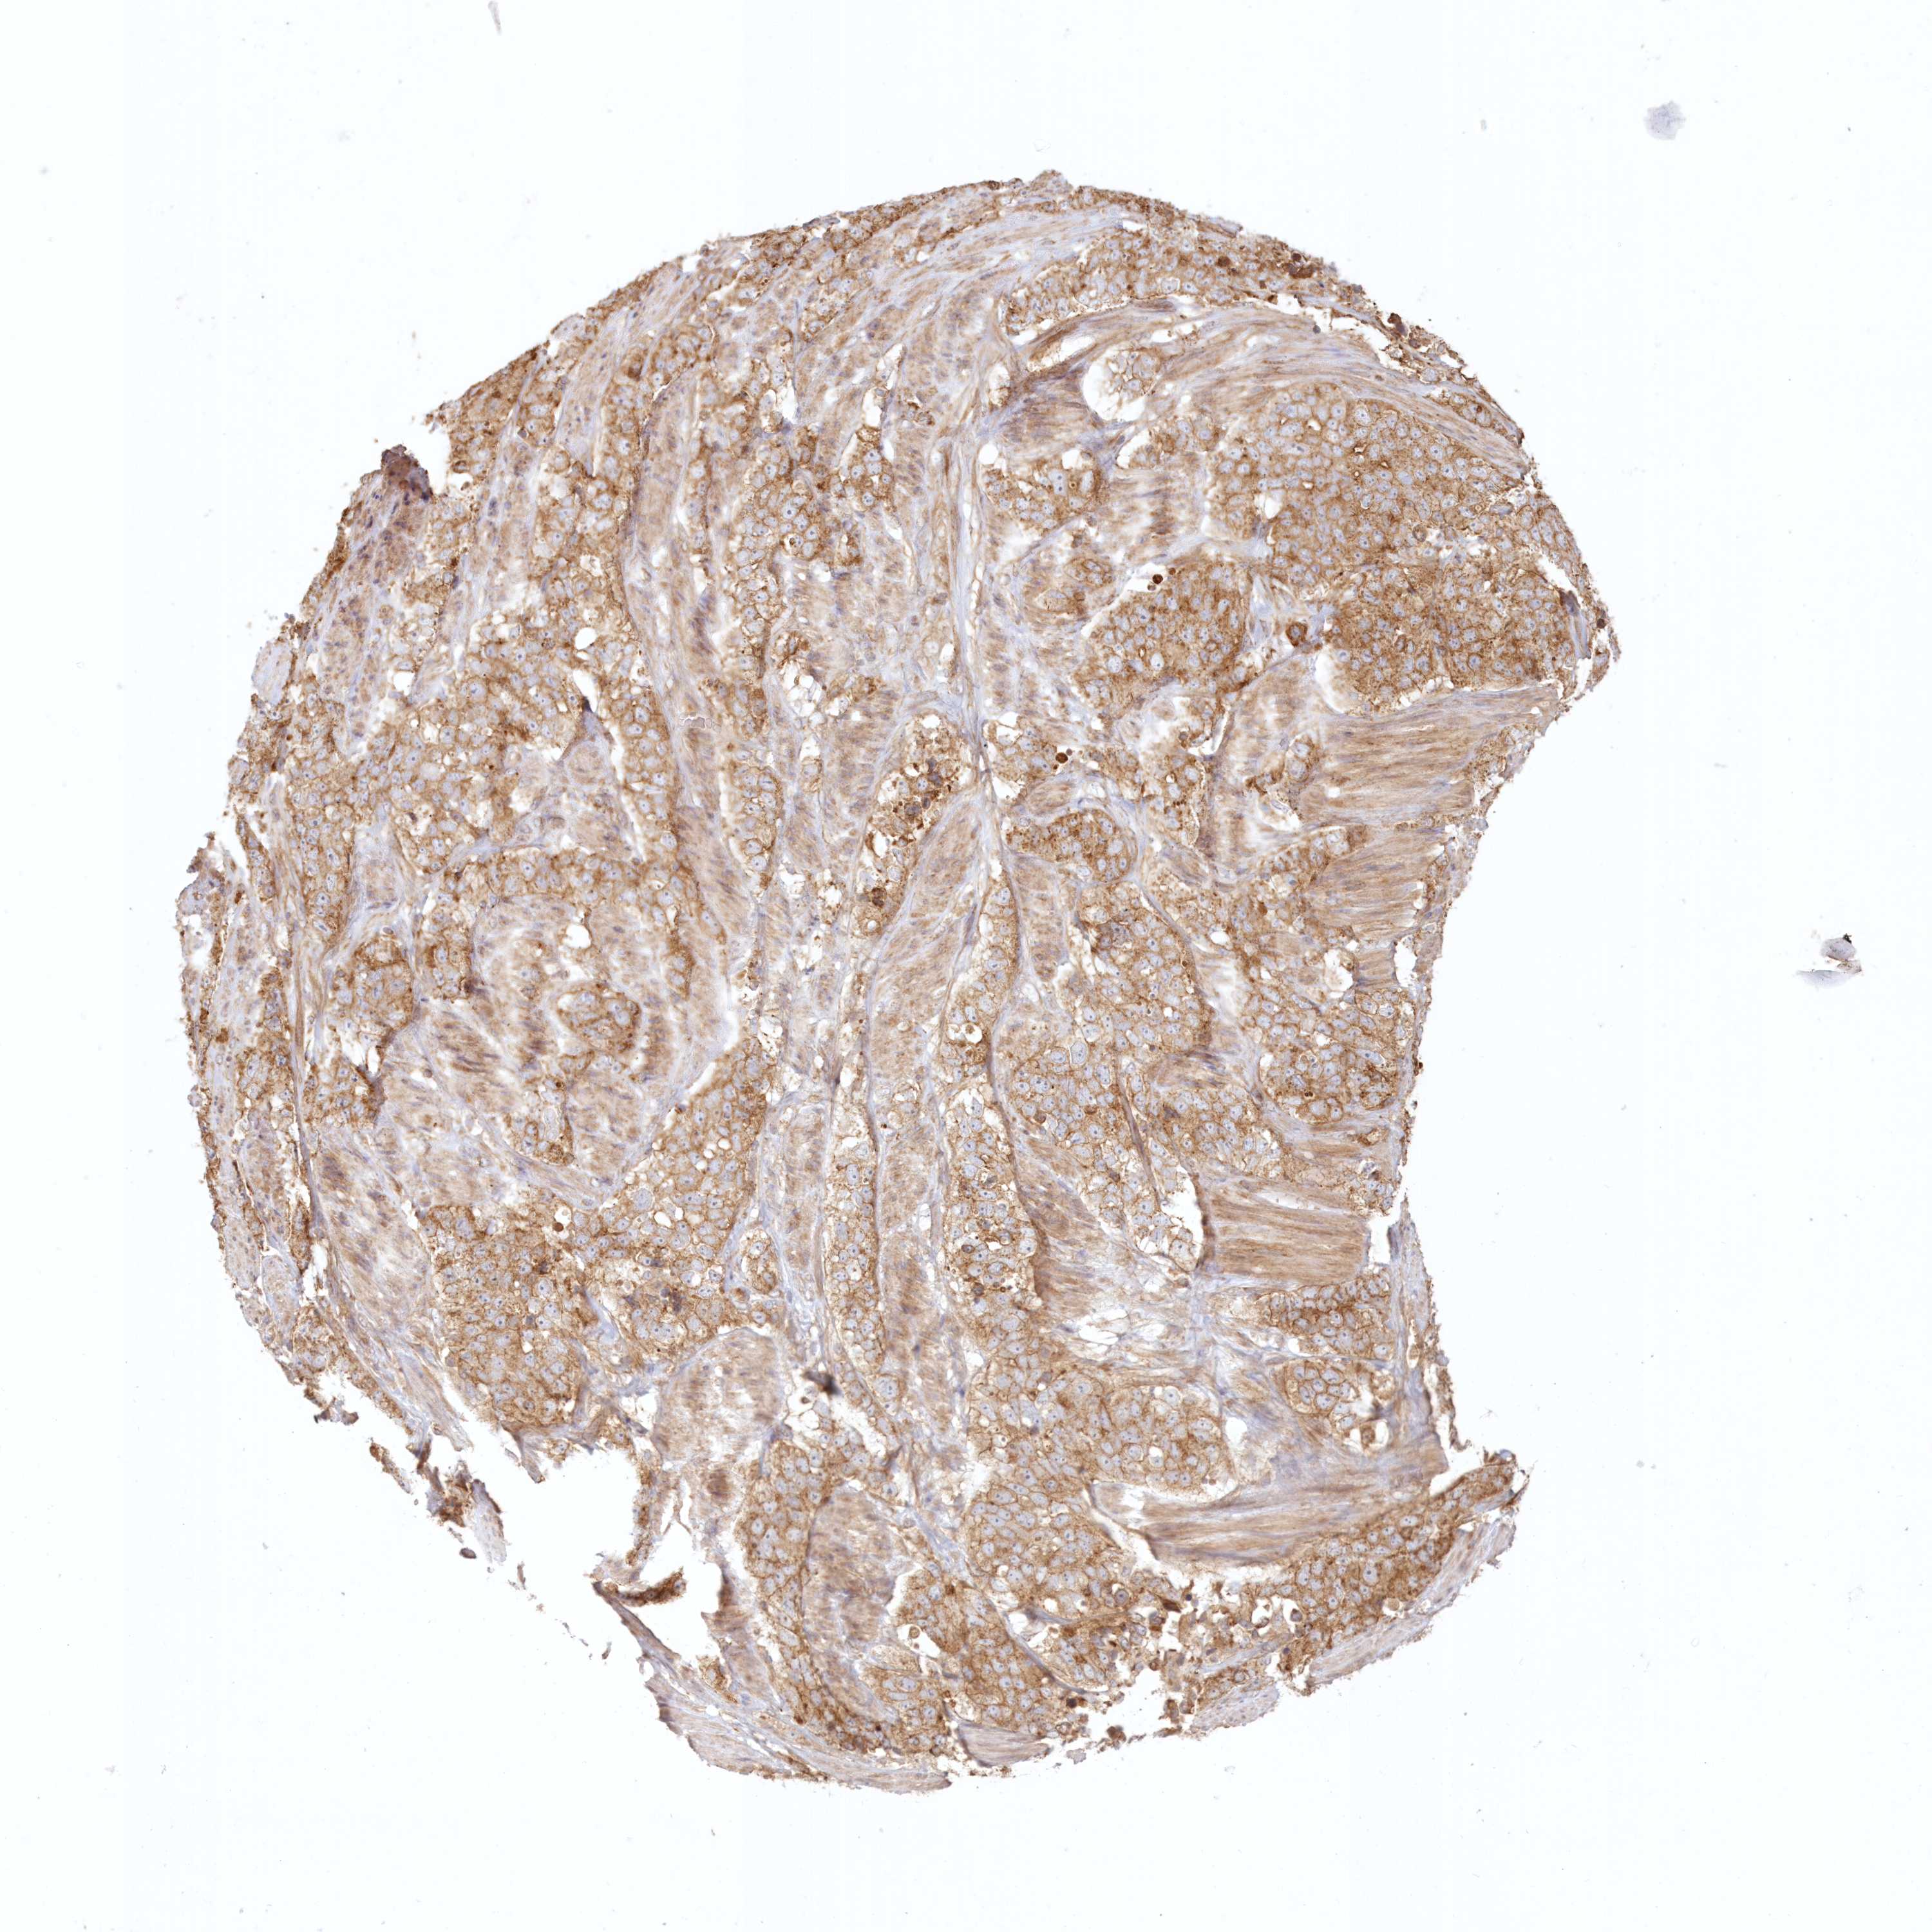

STOMACH CANCER - Protein expressioni

A mouse-over function shows sample information and annotation data. Click on an image to view it in a full screen mode. Samples can be filtered based on level of antibody staining by selecting one or several of the following categories: high, medium, low and not detected. The assay and annotation is described here.

Note that samples used for immunohistochemistry by the Human Protein Atlas do not correspond to samples in the TCGA dataset.

Antibody stainingi

Antibody staining in the annotated cell types in the current human tissue is reported as not detected, low, medium, or high, based on conventional immunohistochemistry profiling in selected tissues. This score is based on the combination of the staining intensity and fraction of stained cells.

Each image is clickable and will lead to virtual microscopy that enables deeper exploration of all samples and also displays staining intensity scores, fraction scores and subcellular localization as well as patient and tissue information for each sample.

Antibody HPA036891

Antibody HPA036892

Antibody HPA061498

Staining

High

Medium

Low

Not detected

Intensity

Strong

Moderate

Weak

Negative

Quantity

>75%

75%-25%

<25%

None

Location

Nuclear

Cytoplasmic/membranous

Cytoplasmic/membranous,nuclear

Adenocarcinoma, NOS